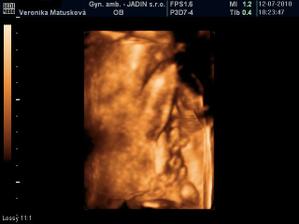

Adamko - 3D/4D

No tot vidno, že je náš syn, sa hanbil a hanbil až sa ukazovať nechcel....ale niekedy sa to podarilo, aj ked to nie je nejaká sláva. Pán doktor nám potvrdil chlapčeka, tak sme radi, vajká ukazoval ako len vedel len toho pipíka stále schovával. Ale je to za nami, pán doktor nás pekne popísal čo je kde, poodmeral nás a povedal, že je všetko v poriadku.